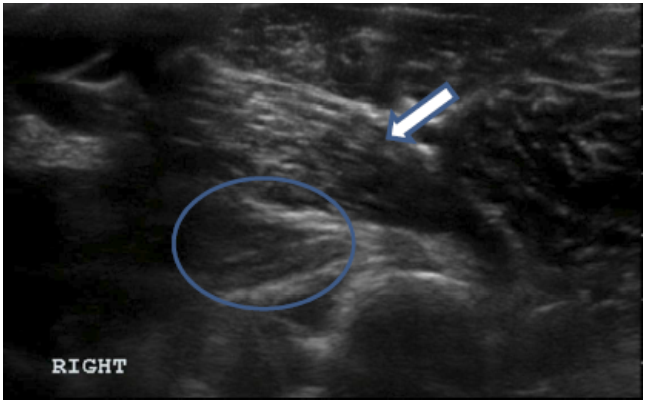

Clinical Evaluation of Iliopsoas Strain with Findings from Diagnostic Musculoskeletal Ultrasound in Agility Performance Canines – 73 Cases